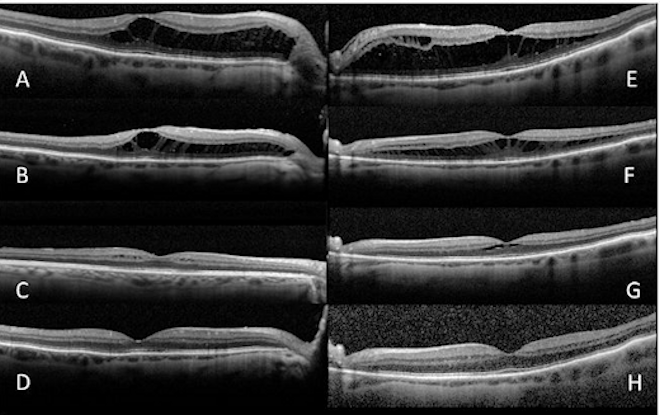

A 78-year-old man complained of bilateral visual acuity loss over the previous 6 months. The best-corrected VA (BCVA) was 20/40 bilaterally. Anterior segment examination showed moderate bilateral cortical lens opacities. Bilateral fundus evaluations and fluorescein angiography were unremarkable (Figure 1 [Fig. 1]). The retina appeared attached in the posterior pole during fundus examination. Optical coherence tomography showed bilateral macular schisis with abundant fluid accumulation in the external retinal layers emanating from the optic disc (Figure 2 [Fig. 2]). No vitreous traction was observed. Assessment of macular function by perimetry or microperimetry or patient referral to a neurologist was not considered of interest. Both eyes underwent surgery that included phacoemulsification, intraocular lens implantation, and vitrectomy. Laser, gas exchange, or retinal fenestration was not performed as adjuvants intraoperatively. A posterior vitreous detachment (PVD) was detected intraoperatively in both eyes. An interval of 3 months was allowed between both surgeries in each eye. Progressive fluid resorption and improvement in VA were observed bilaterally; 12 months postoperatively the bilateral BCVA was 20/20 and the macular schisis resolved bilaterally (Figure 2 [Fig. 2]).

Figure 2: A, Macular schisis of the right eye. B, C, D, Progressive resolution of macular schisis in the right eye. E, Macular schisis of the left eye. F, G, H, Progressive resolution of macular schisis in the left eye.